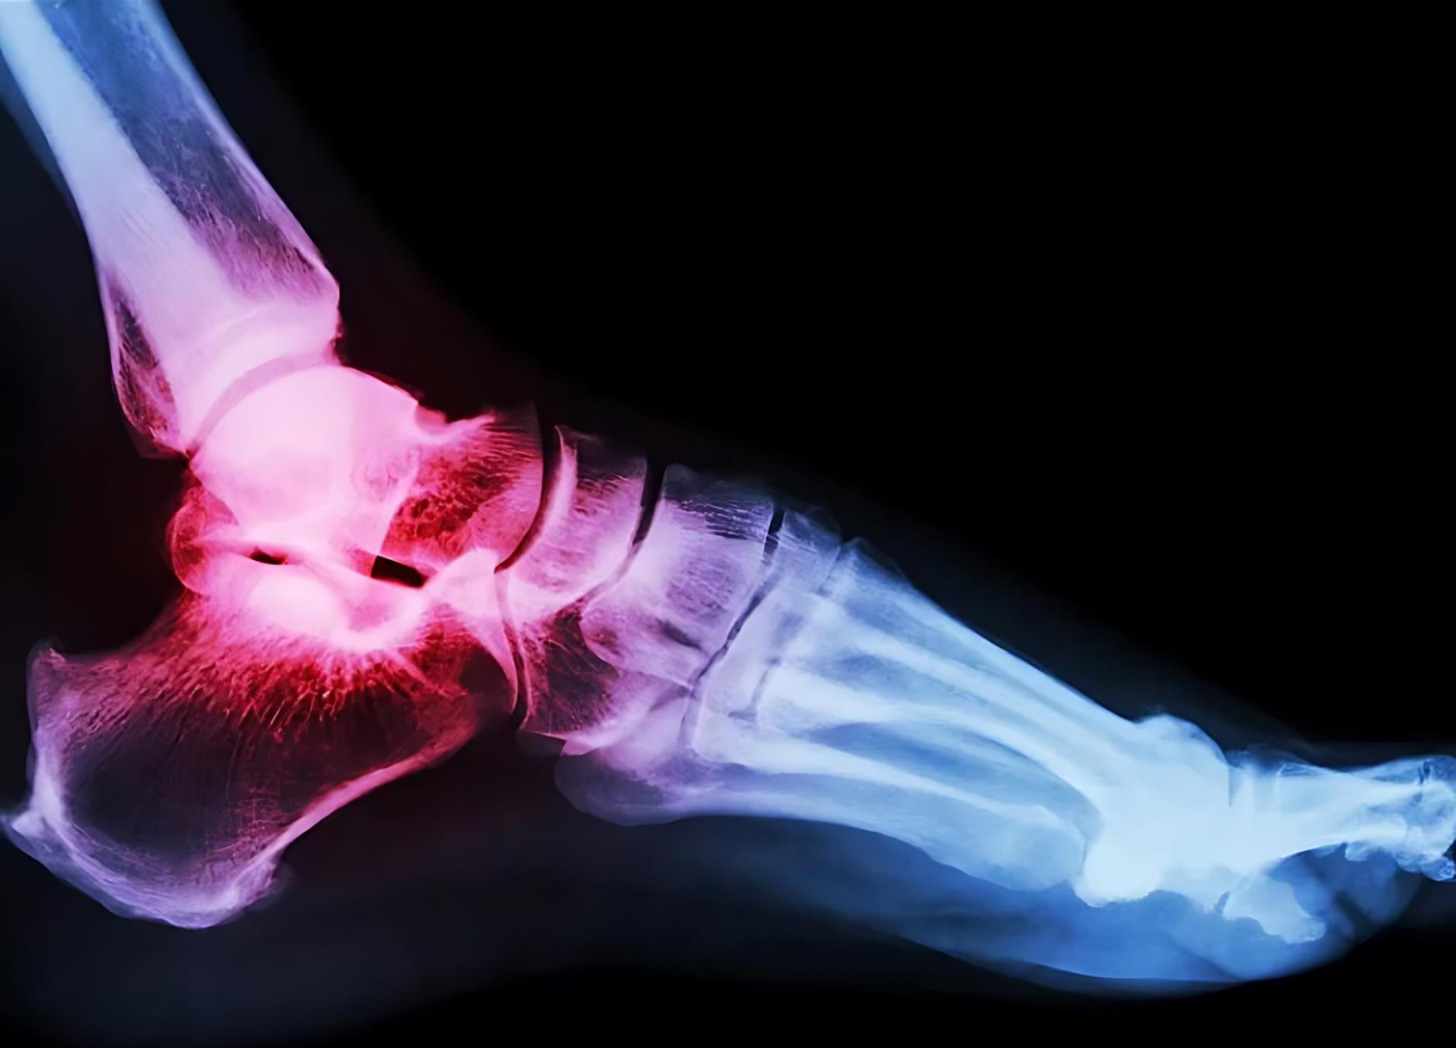

Despre gută

✅ BOALA COOL A BOGAȚILOR

Despre gută, super frumos explicat ca să nu mai scriu 100 de paragrafe vă invit să-l vizualizati, e super!